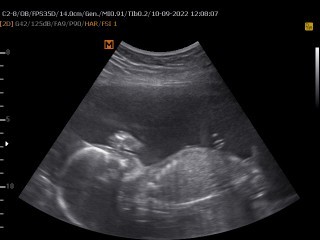

9ม.ค ค่ะผู้ชายแม่บ้านนี้นอนลำบากมากค่ะน้องดิ้นเก่ง